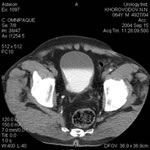

Исследование стенок мочевого пузыря